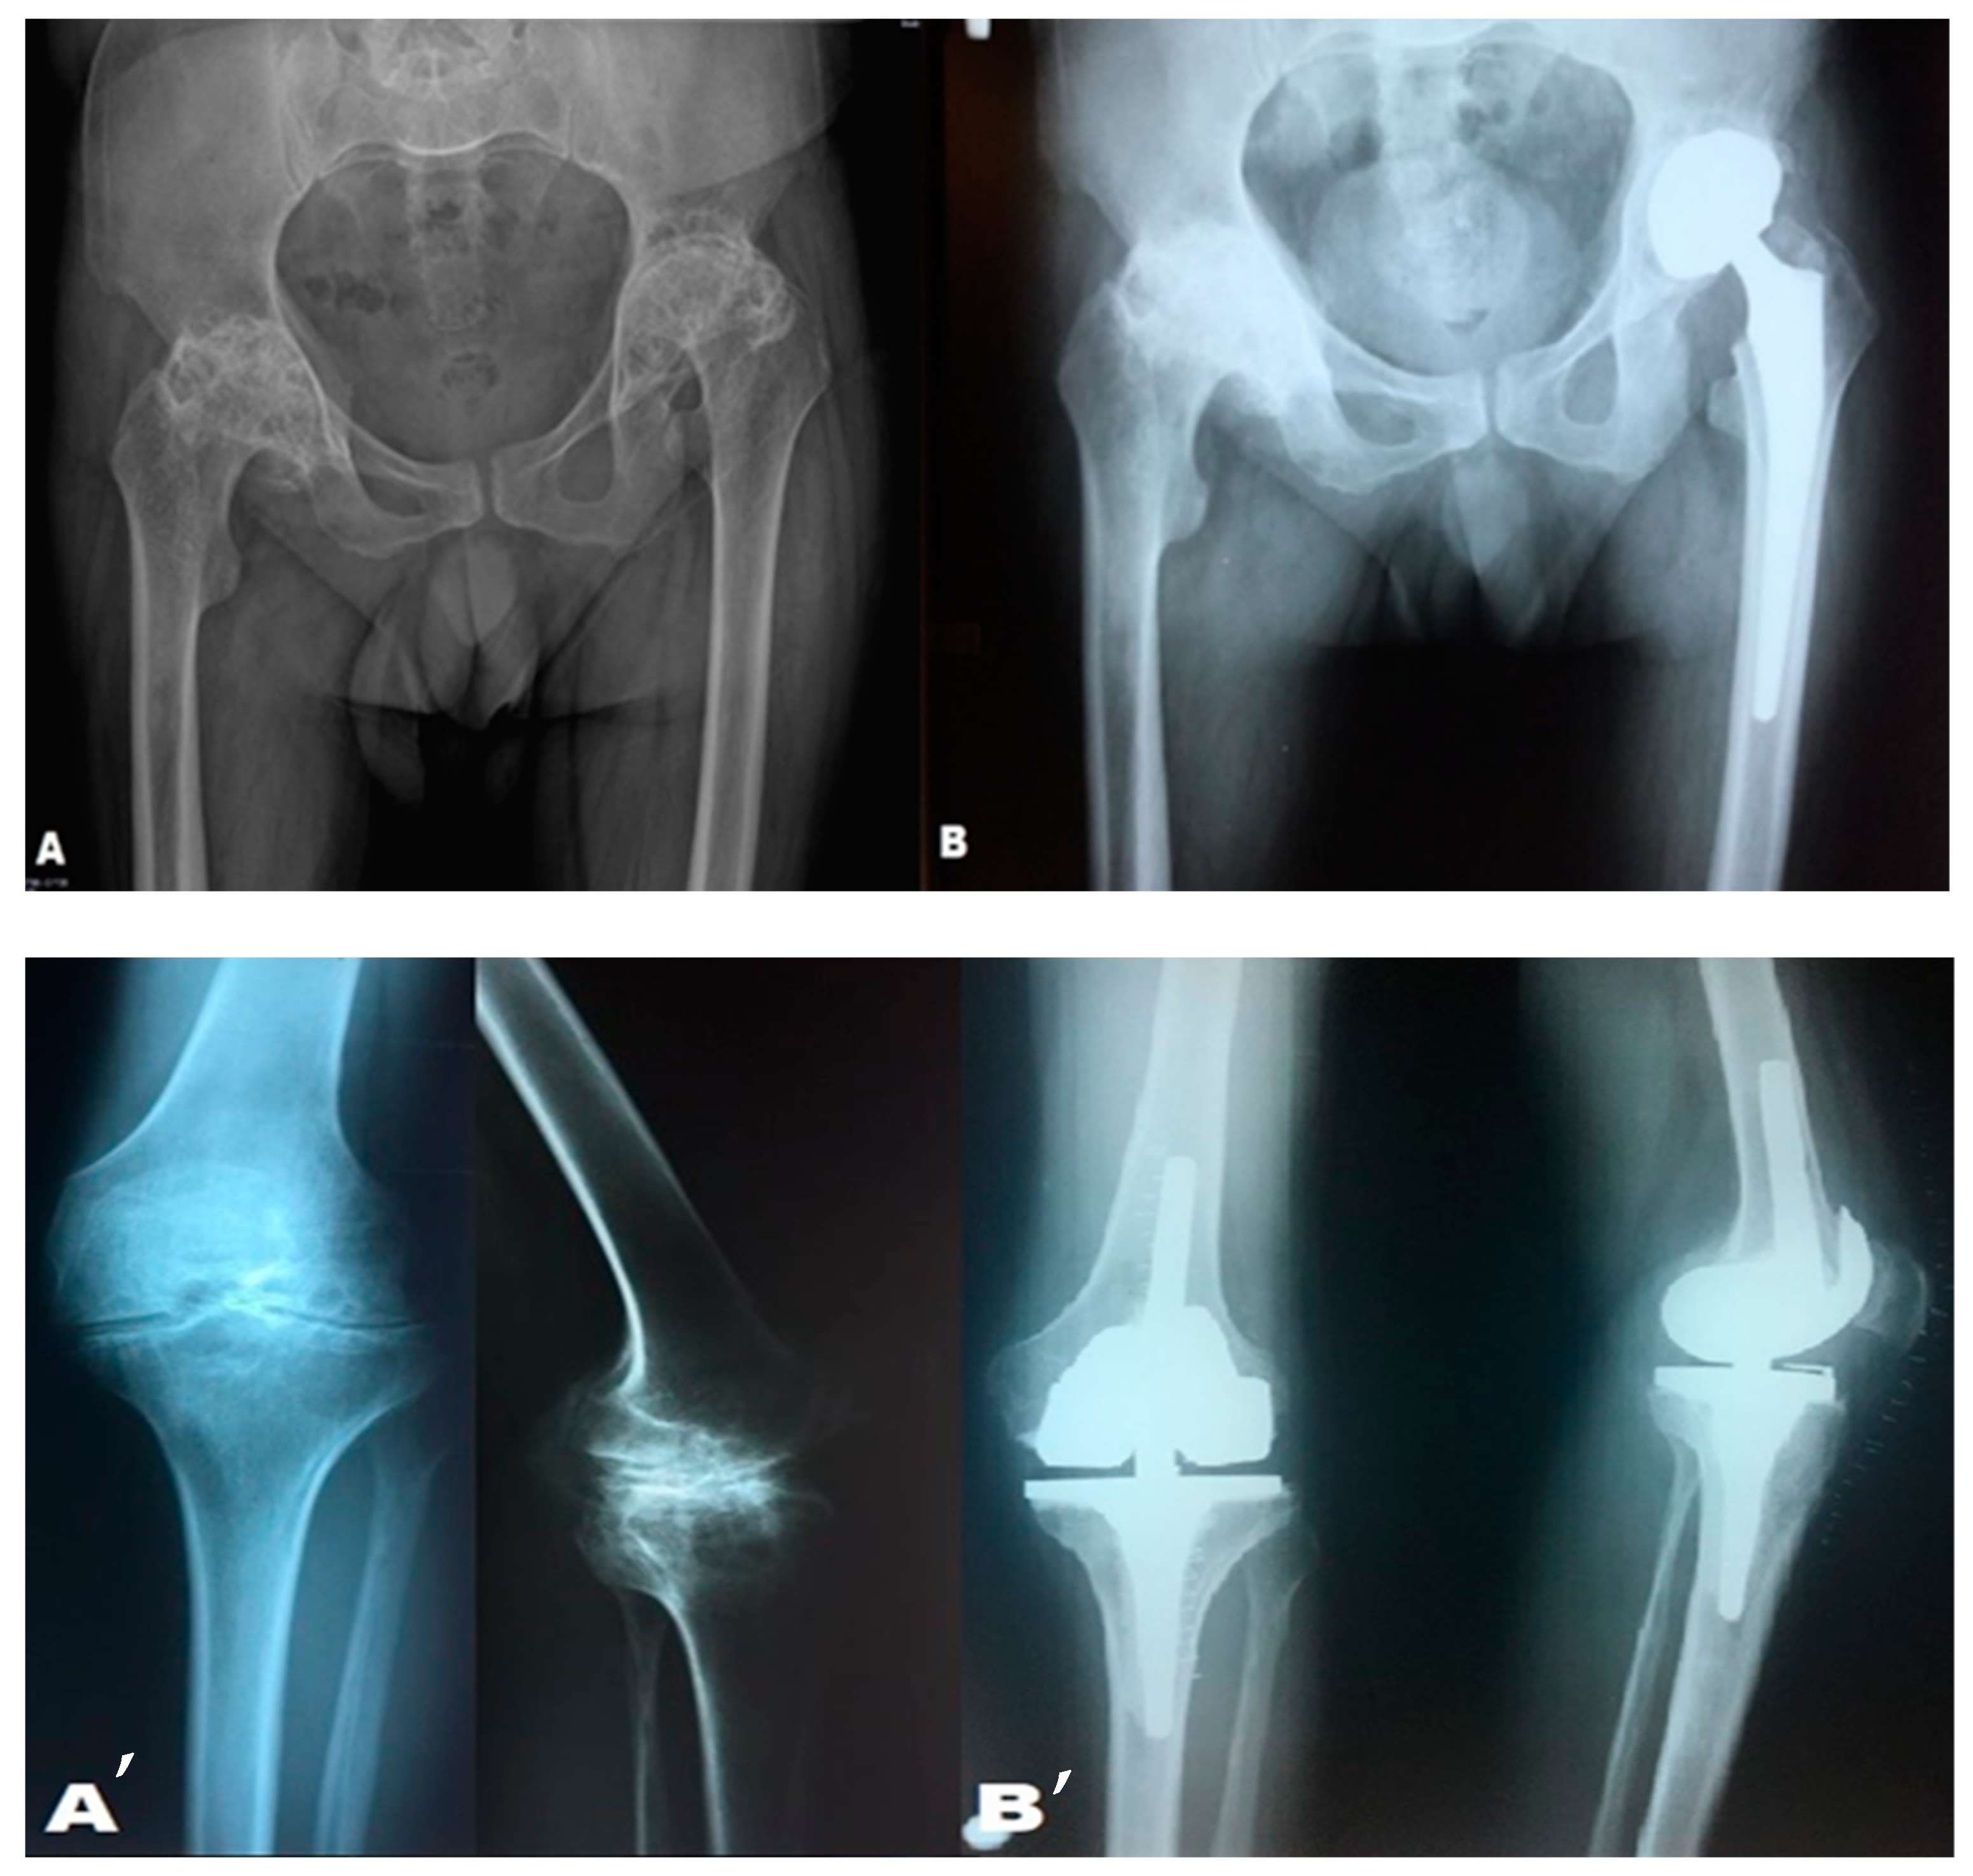

3.3. Surgical Treatment and Subgroup Analysis

- For the knee, 36.7% of cases underwent surgery, and 26.7% are currently awaiting surgery (p = 0.003).

- For the ankle, 33.3% of cases underwent surgery, and 33.3% are awaiting surgery (p = 0.012).

- For the hip, 45.5% of cases underwent surgery, and 27.3% are awaiting surgery (p = 0.049).

3.6. Arthroplasties Performed in Patients with Severe Type A Hemophilia

3.7. Total Hip Arthroplasty Performed on a Patient with Moderate Type B Hemophilia and a Bleeding Phenotype